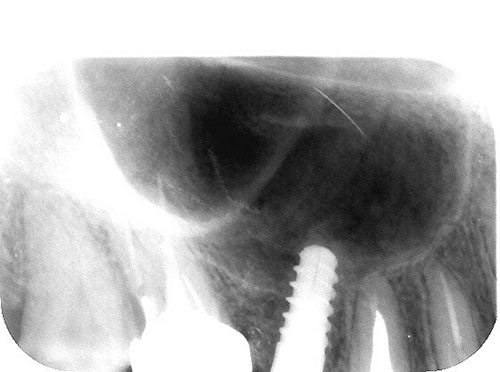

Mientras dichos movimientos ortopédicos se producen (período que supondrá otros seis meses), estudiamos los actos quirúrgicos a realizar en los cuatro implantes que pondremos. De acuerdo al estudio Desatascan realizado observamos tres situaciones diferentes: 1º-El Primer Molar Inferior Izquierdo, lo instalamos mediante Cirugía Minimamente Invasiva , con la aplicación de una Férula Quirúrgica Obtenida de los datos del scanner tratados con un programa de CMI (Cirugía Minimamente Invasiva), previa prueba en un modelo estereolitográfico, ya que la altura ósea era apenas de 9 mm. 2º- El Primer Molar Superior Derecho, se implantará mediante una ligera Elevación Atraumática (Trans alveolar) de Seno una vez logrado el espacio mesio distal necesario. 3º- El Incisivo Central Superior Derecho ausente, cuenta con un sustrato óseo prácticamente inexistente. El espesor de la tabla era de menos de 2 mm. Los caminos posibles a seguir para contar con una Rehabilitación de piezas independientes son dos: Optamos por esta segunda opción por ser menos cruenta y no necesitar de una zona dadora. Técnica esta que pondremos en práctica en dos etapas diferidas: 1º-Incisión horizontal palatinizada, incisiones peri rodetes gingivales e incisiones de descarga. Dilatación que comenzamos con dos incisiones de descarga sobre la cortical vestibular realizadas con disco. y el comienzo de la dilatación propiamente dicha mediante una hoja de bisturí, para luego seguir con un periostótomo . Recién después de alcanzada una cierta separación de la cortical vestibular de la palatina, empezamos con los dilatadores roscados. En este punto podríamos haber utilizado sin riesgos un Implante de 3,8 mm de diámetro, pero a fin de mejorar la estética del pilar emergente decidimos rellenar con material osteoconductor y osteoinductor (BiOss) y cubrir mediante membrana reabsorvible ( Bio Guide). 2º-Implantación seis meses después. Mientras se van cumpliendo los tiempos antes mencionados, y comprobamos reiteradamente la funcionalidad de la oclusión con los provisorios, tomamos impresiones definitivas y construimos primero el maxilar inferior, para definir en primer término la porción inferior de la Guía Anterior., y a nivel posterior Curvas y Microplanos. Para luego realizar los cuadrantes premolar- molar del superior: La espera de la regeneración ósea y sus tiempos pertinentes, más la espera de los tiempos de la implantación, nos obligaron a modificar las etapas del protocolo D.AT.O de manera de mantener la –D- mediante el sector superior de la GA. en provisorios, mientras fuimos resolviendo en forma definitiva los demás sectores. Ya pasados los meses necesarios para recrear un hueso adecuado en el área del Incisivo Superior Derecho, procedemos a resolver la implantación de dicha zona, observando que todo el esfuerzo dedicado al mismo había sido inútil, ya que la formación de hueso se produjo minimamente. Cuatro meses después tomamos impresiones del sector Antero Superior de la Guía Anterior, incluyendo el arrastre de un transfer . Seguimos modelando la encía con un nuevo juego de provisorios. Y se construye entonces el sector superior de la Guía Anterior. Se efectúa un control radiográfico a los 6 meses. Se ha intentado mostrar en esta Rehabilitación, que a pesar de las distintas circunstancias de cada paciente, siempre debemos tener en cuenta la necesidad de ejercer la DESOCLUSIÓN del caso como prioridad número uno, para luego perseguir la ALINEACIÓN TRIDIMENSIONAL de las arcadas y obtener así una OCLUSIÓN equilibrada. D.AT.O. ES EL PROTOCOLO QUE DEBEMOS SEGUIR EN TODA REHABILITACIÓN. BIBLIOGRAFÍA 1)William Mc Horris,B.S.,D.D.S. Oclusión. Con especial énfasis sobre :El rol funcional y parafuncional de los dientes anteriores. 2)Von Spee , Craff(Anatomista alemán, describió la curva de compensación de la articulación de molares y premolares).CURVA DE SPEE 1.89 3)Stuart,D.”Some aspects of the inervation teeth.”Procedings of Royal Society of Medicine.20:1675,19274)Muhleman,H. y Savdir,S”Tooth movility-its causes and significance”Journal of Periodontology ,36:153,Marzo ,Abril,1965. 4)Muhleman,H. Y Savdir,S”Toothmovility its causes and significance” Journal of Periodontology,36:153,marzo,abril,1965. 5-Oclusión y Diagnóstico en Rehabilitación Oral. 6-Anatomia Odontológica. 7-A contribution to the study of the movementes of the mandible. 8-Celenza F.W, Nadeskin J.F.,Oclusión.Situación actual. 9-D´Amico 10-Dawson P.E. 11-Huffman –Regenos. 12-Hobo S.-Takayama H.A. 13-Lucia V.O 14-Mc Horris. 15-Mc Horris. 16-Stuart C. 17-Vartan Veshnilian 18-Alvarez Cantoni H. AUTOR:Ratificación del Protocolo en Rehabilitación Bucal a pesar de las incidencias propias de cada caso clínico. A propósito de un caso.

No obstante pudimos implantar satisfactoriamente mediante un implante de 4.2 mm. de ancho y 14 mm. de largo, con una nueva R.O.G.

El implante se encontraba perfectamente según comprobaciones radiográficas y clínicas al sondeo.